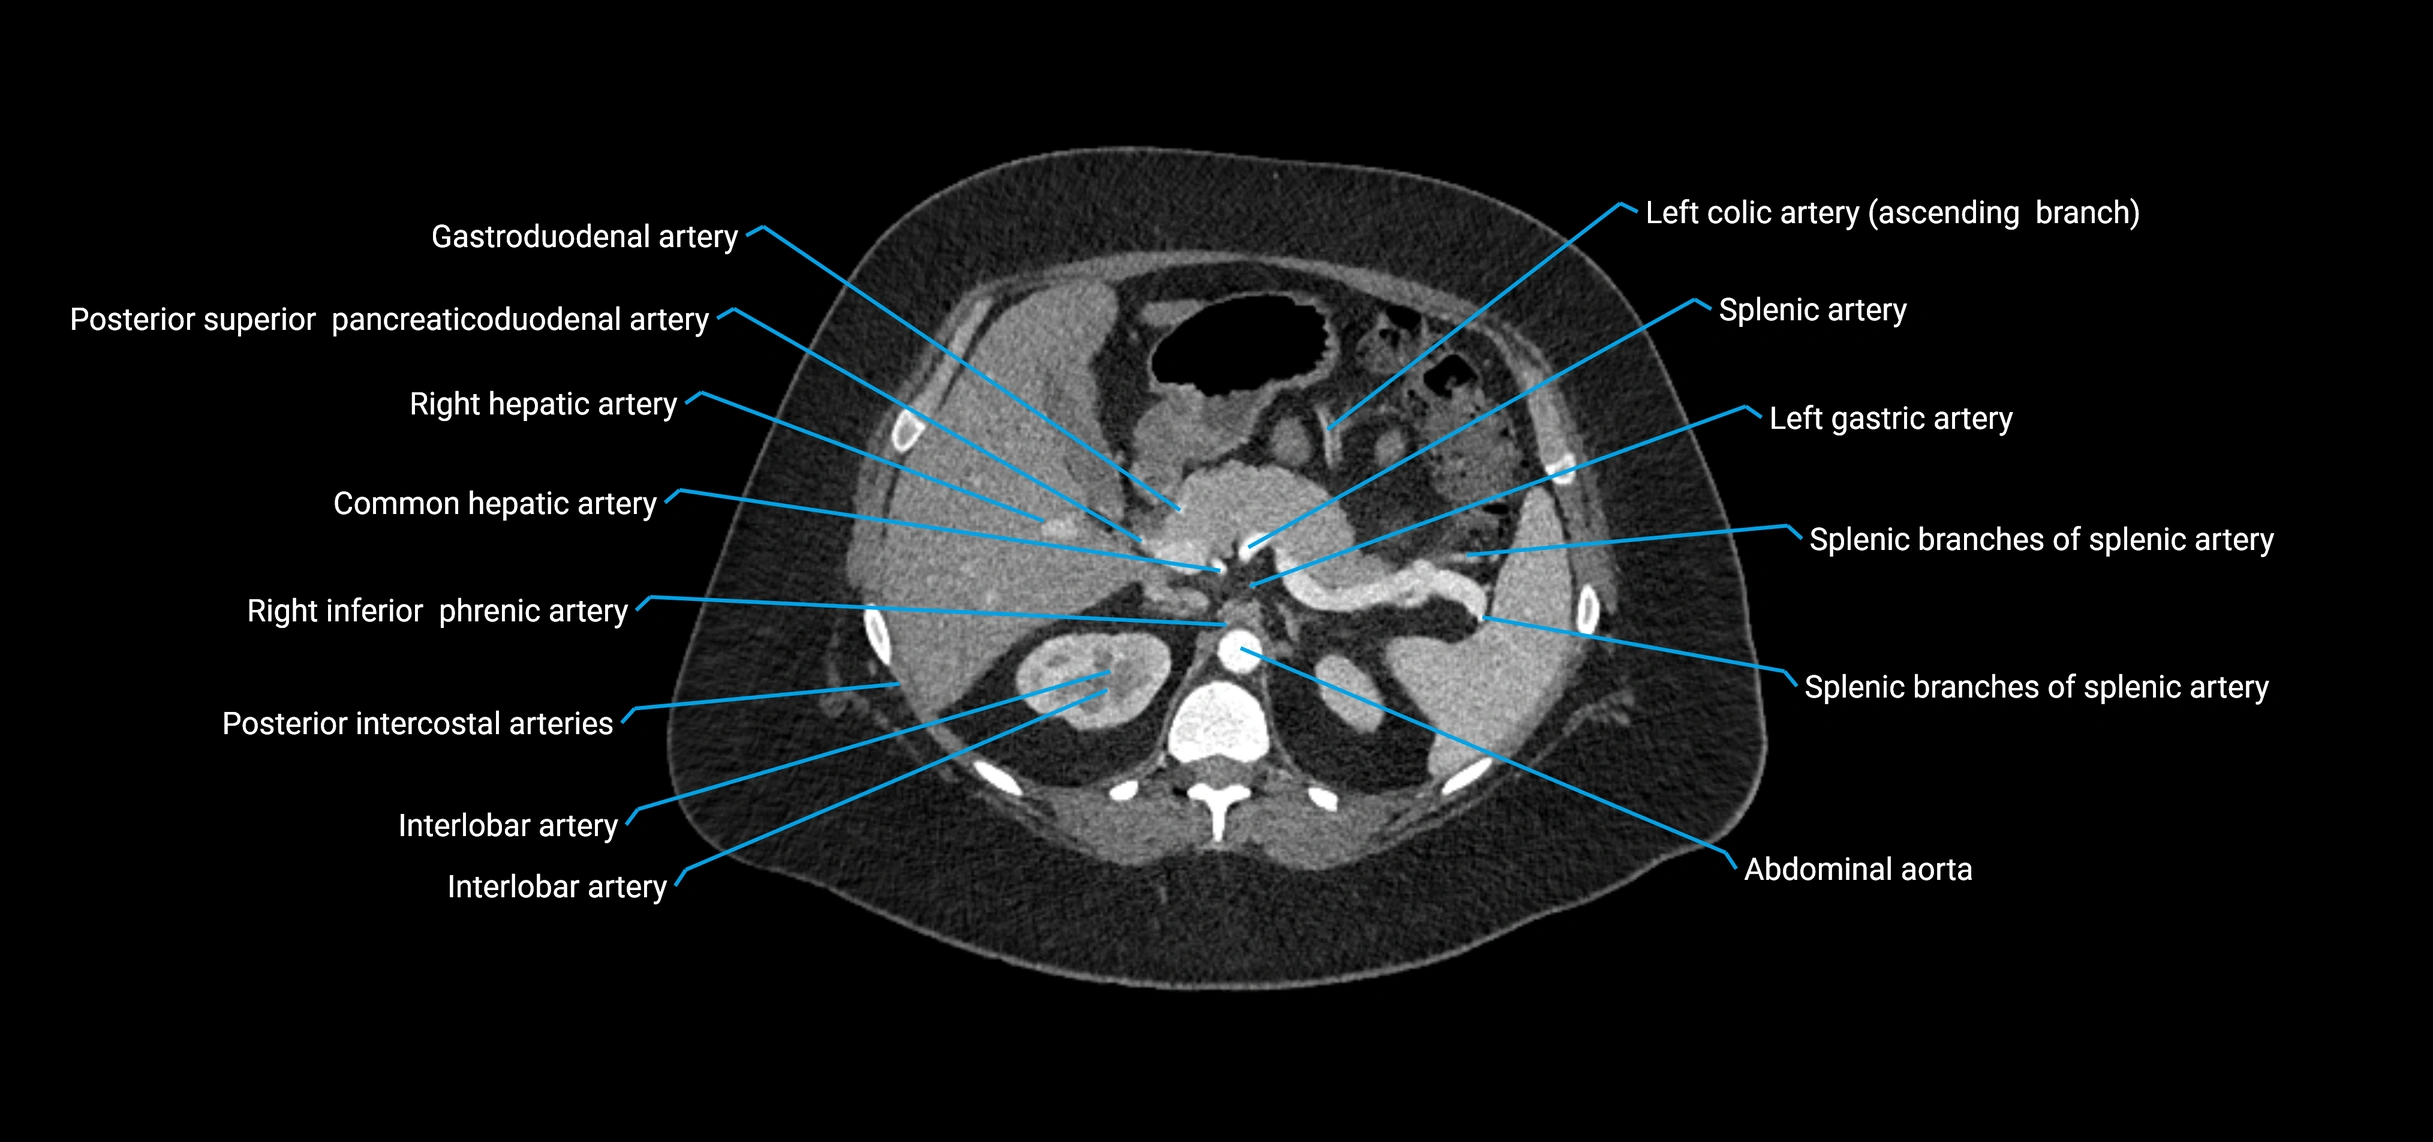

Contrast-enhanced CT (CTA):

• Gold standard for abdominal aortic imaging

• Provides excellent detail of lumen, wall, aneurysm, thrombus, and branch vessels

• Multiplanar and 3D reconstructions help in aneurysm measurement, stent graft planning, and dissection evaluation

• Detects acute rupture, traumatic injury, or occlusion with high sensitivity